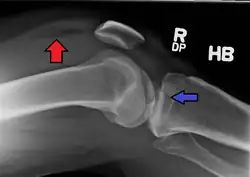

Lipohemarthrosis (presence of fat and blood from bone marrow in the joint space after an intraarticular fracture) seen on X-ray in a person with a subtle tibial plateau fracture

Lipohemarthrosis due to a tibial plateau fracture